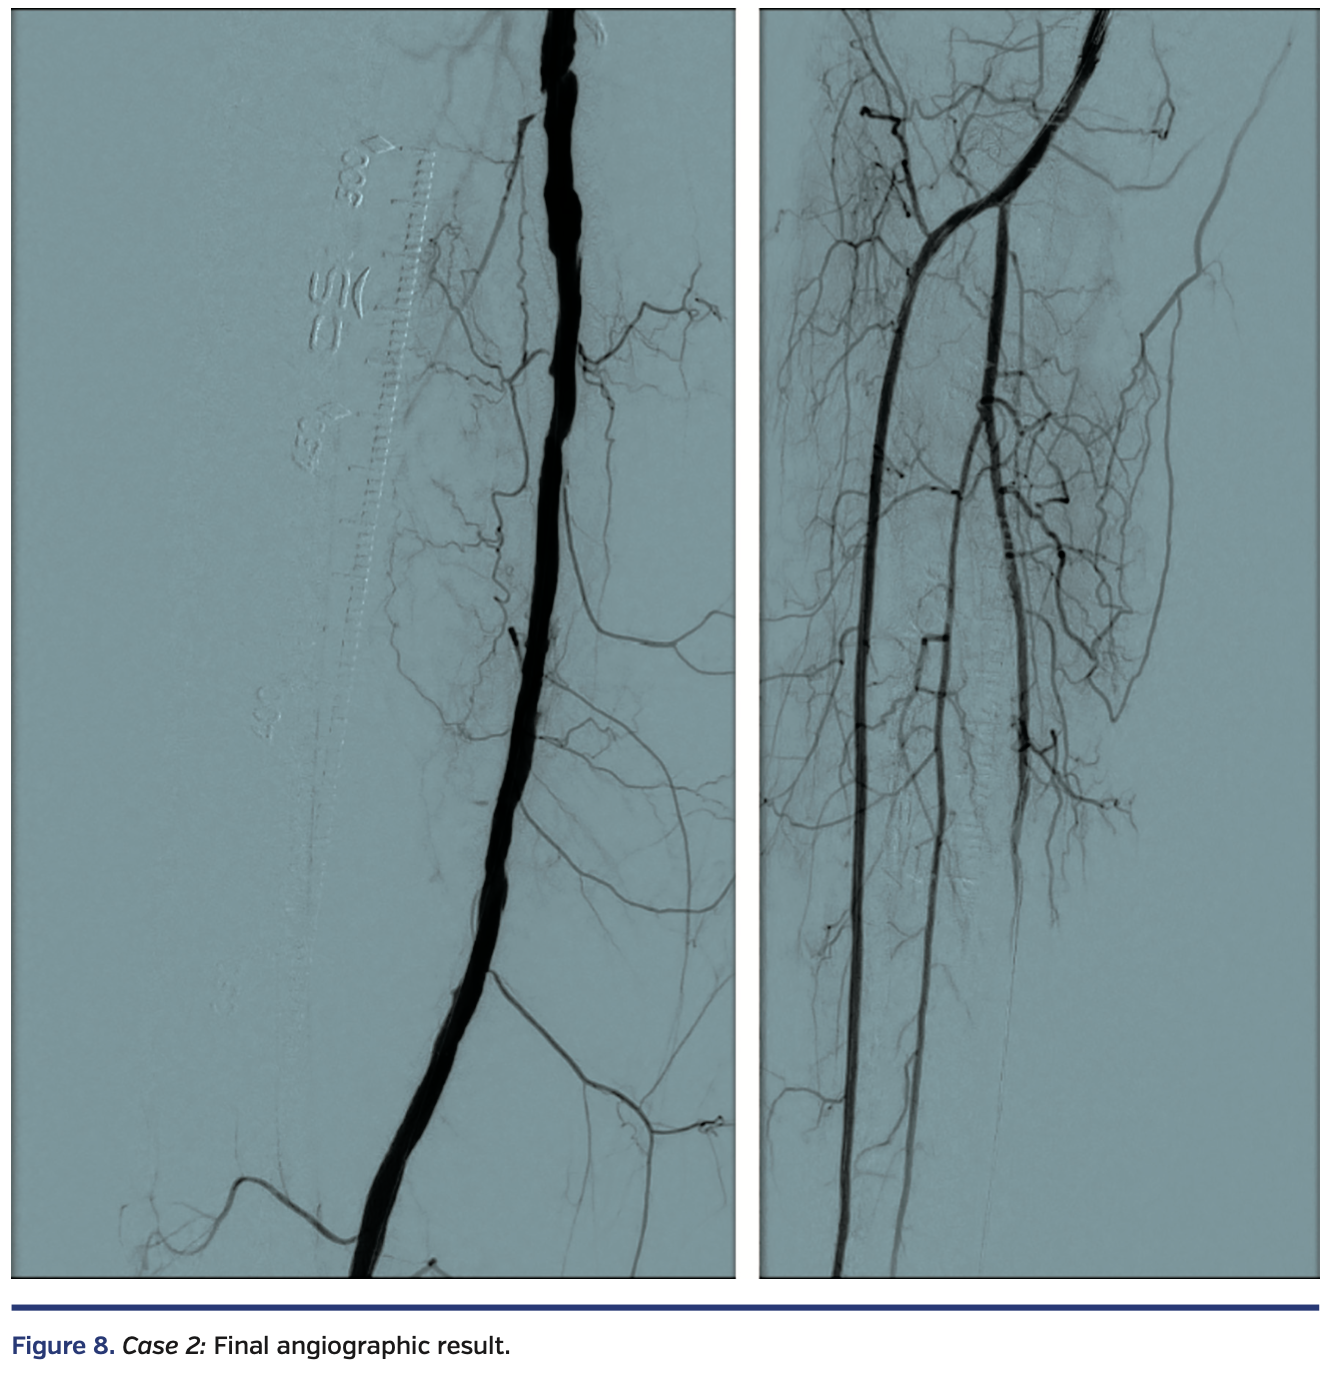

Sequential balloon angioplasty in the anterior tibial artery was performed with 2.0 mm and 4.0 mm Coyote balloon (Boston Scientific). Kissing balloon angioplasty of the popliteal artery, proximal anterior tibial, and tibioperoneal trunks was performed with long 3 mm balloons, followed by drug-coated balloon angioplasty of the right femoropopliteal segment with a 6 mm x 250 mm IN.PACT Admiral drug-coated balloon (Medtronic). There was restoration of normal flow in all treated segments (Figure 8), with a warm foot and a palpable dorsalis pedis artery at the end of the case.